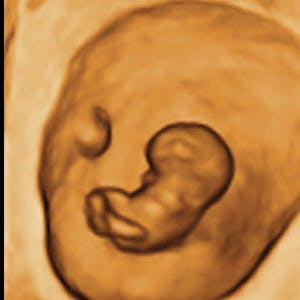

Gravid

Vi gør en dyd ud af at klæde dig godt på både før, under og efter din graviditet. Vi ved, at der kan komme mange spørgsmål til din graviditet, fødsel, amning, din babys udvikling og mange flere emner, derfor har vi samlet guides, tips & tricks samt læsernes egne fortællinger i dette gravid univers.